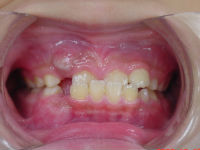

反対咬合<うけぐち>は

矯正の分野では低年齢でもっとも気がつきやすい症状です。

今回の症例は小学3年生です。

治療の方向性として、受け口に対するだけでなく、

トータルに咬み合わせのバランスを改善していく事により

特に鼻の機能の向上を狙っています。

治療期間は1年6カ月です。

独自の方法及びムー・i-3等によって改善しています。

治療前 治療後